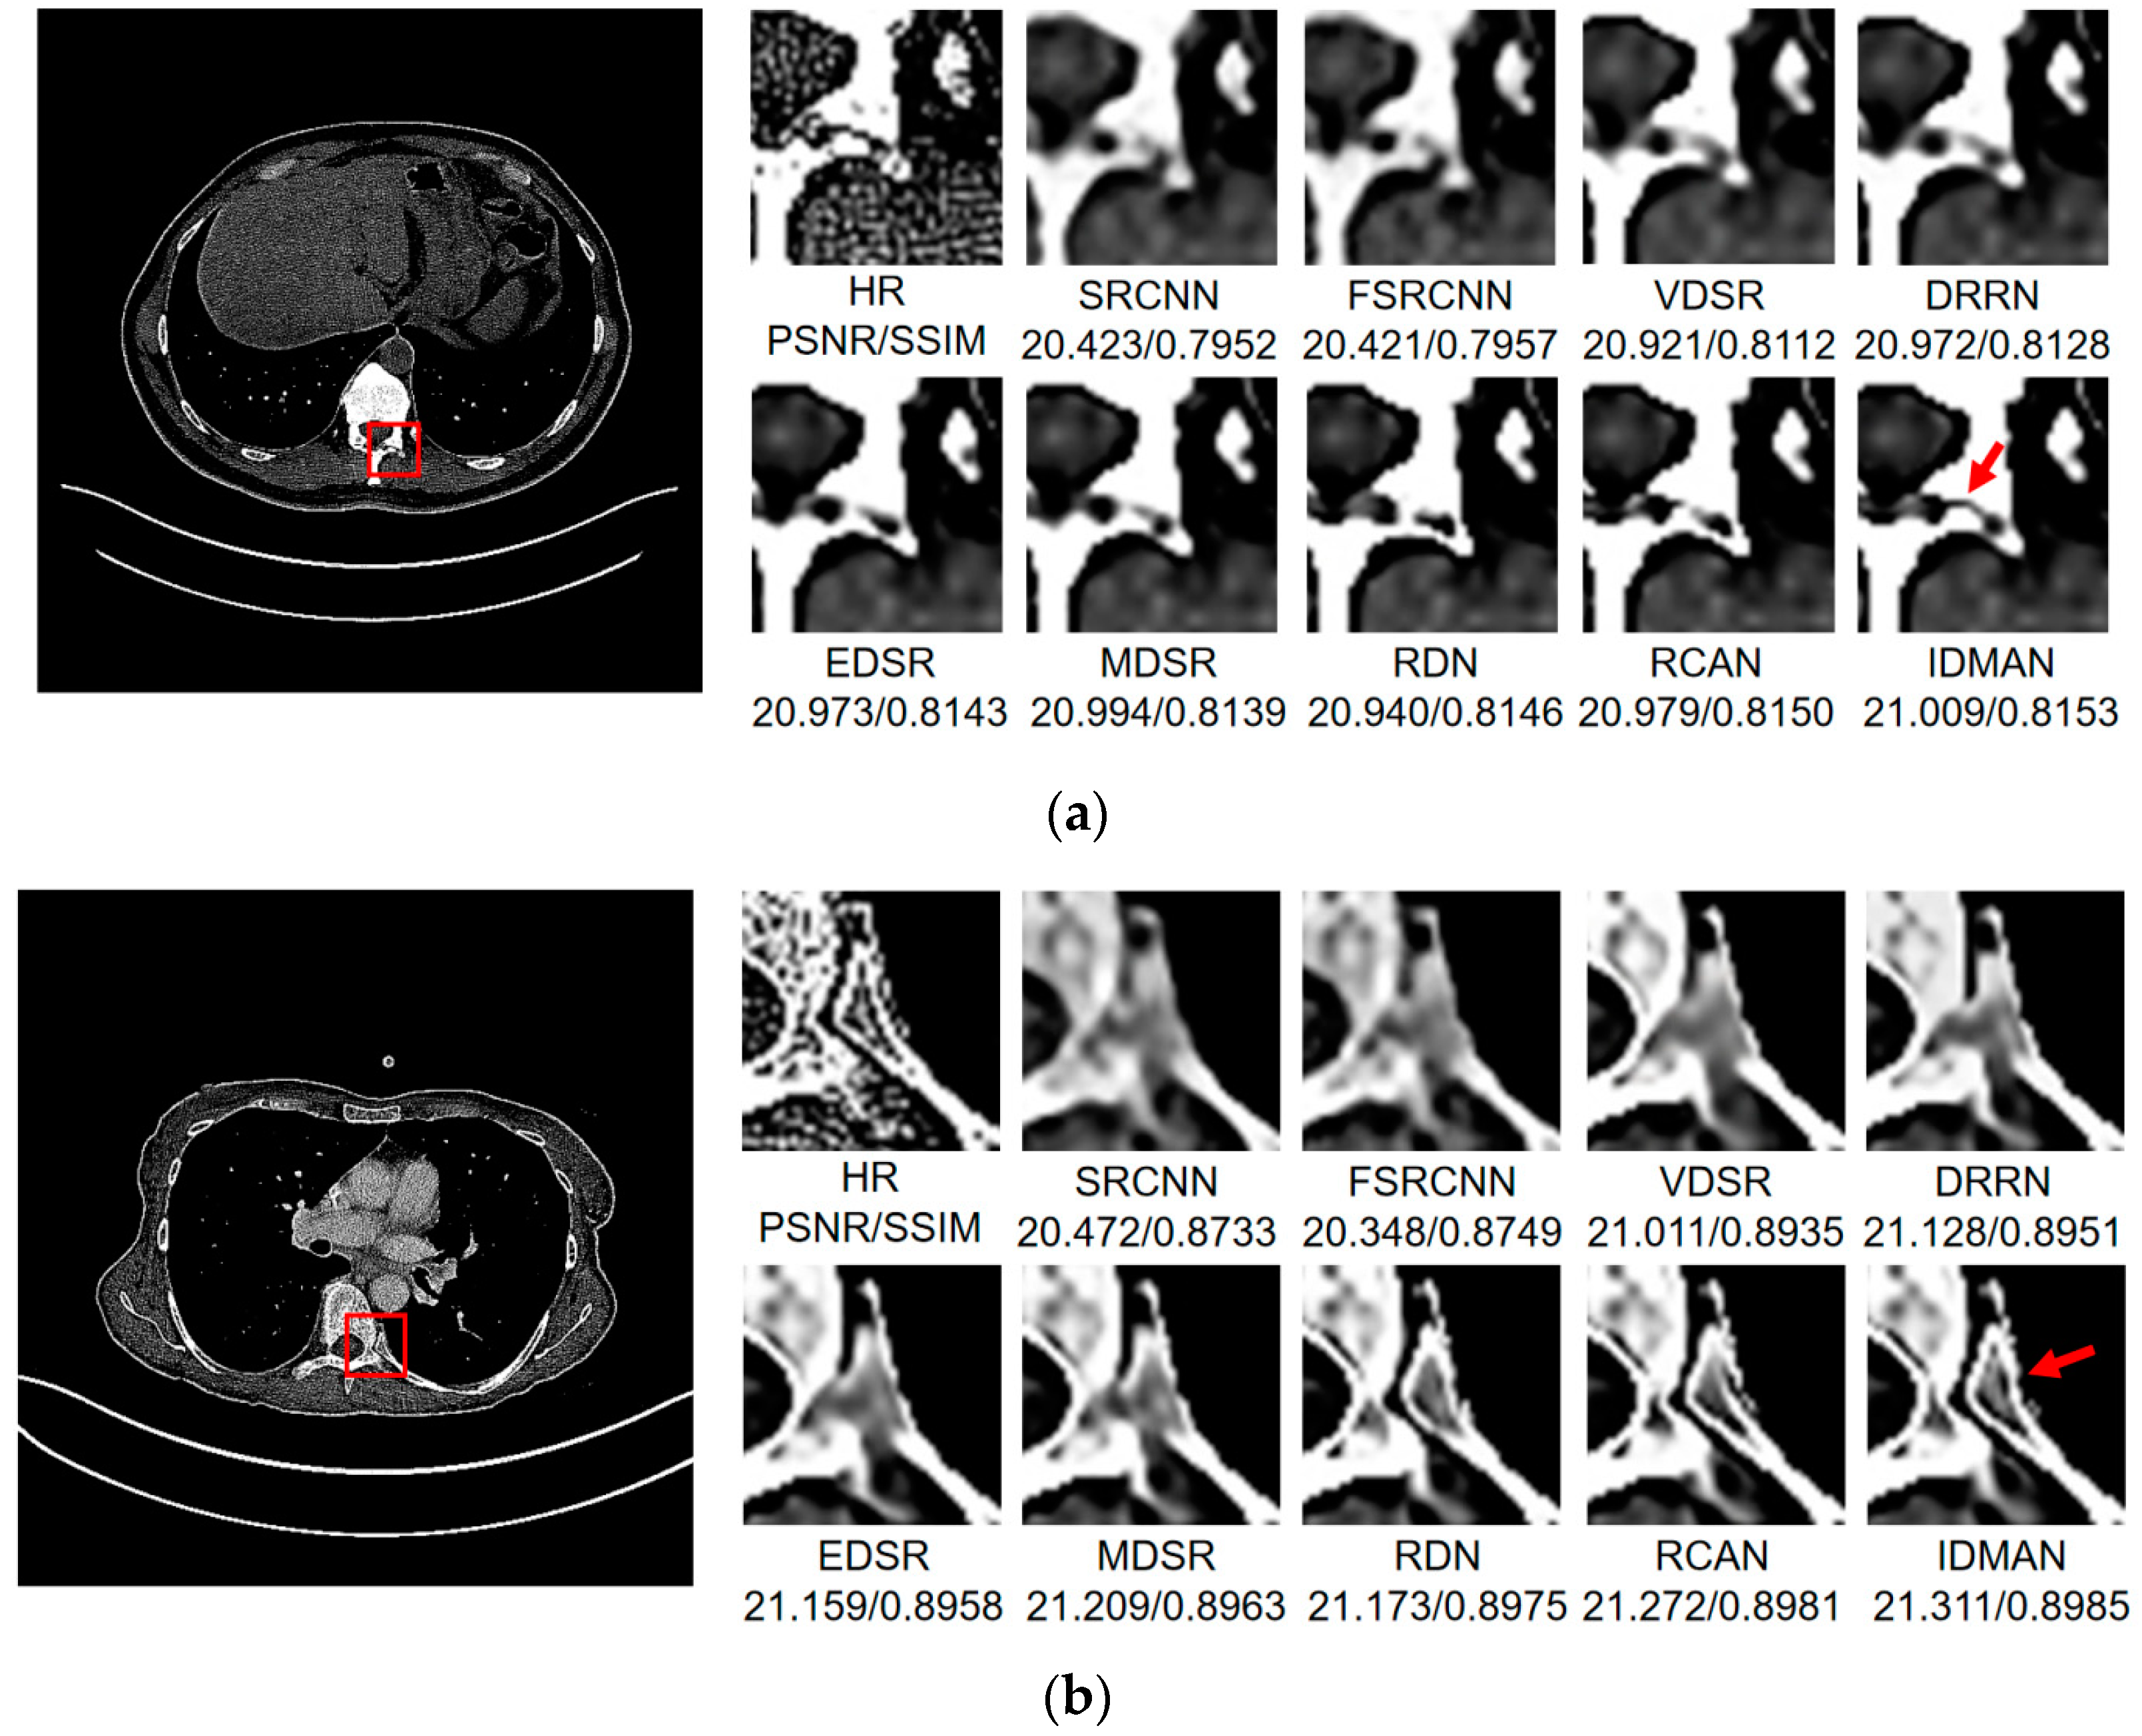

Visual Results: In order to analyze the reconstructed CT image from the subjective visual effect, we select several groups of CT image for a contrast display in Figure 8, Figure 9 and Figure 10.

Figure 10.

Images (a,b) show the visual results of different algorithms on DeepLesion testing set for scaling factor .

On the whole, The IDMAN proposed in this paper can reconstruct clearer edges and more realistic textures. Under the scale SR, as shown in Figure 8a, it is clear that the image reconstructed by IDMAN has a more realistic texture and a better visual effect. In Figure 8b, the reconstructed SR image can restore more truthful details than other methods. In Figure 8c, the image reconstructed by the contrast method is blurred, while the reconstructed result by our method has sharpener edges and more detail. In Figure 8d, the reconstructed image has a clearer and smoother edge. Under 3 scale SR, from Figure 9a, it can be seen that the structure of the reconstructed image by other algorithms is more unclear, while the reconstructed result of IDMAN is more realistic. In Figure 9b, our reconstructed image has a more restored effect with clearer and more accurate contour lines, compared to other methods. Under the scale SR, we can observe, from Figure 10a, that the result of our method can better restore the original information and is more similar to the original image. In Figure 10b, it is clear that IDMAN can reconstruct a clearer edge but the images of other methods appear more blurred. Our proposed model achieved better results in the CT image dataset. The reconstructed CT image of our method has more details, and PSNR and SSIM also achieved higher scores.

It can be clearly observed that the reconstruction effect of SRCNN with only three layers is the worst among these methods based on deep learning, with problems such as blurring, artifacts, a lack of detail, unclear edges and so on. The later improved models are becoming more and more complex by deepening the network or using different learning strategies, and the reconstructed results have a clearer structure which is better than SRCNN. Additionally, our IDMAN has a superior learning ability, and the reconstructed results become to have more details and sharper edges. The better visual reconstruction results also prove that we can use information distillation and multi-scale attention to help the network make full use of the feature information more effectively, and capture more information to restore more details.